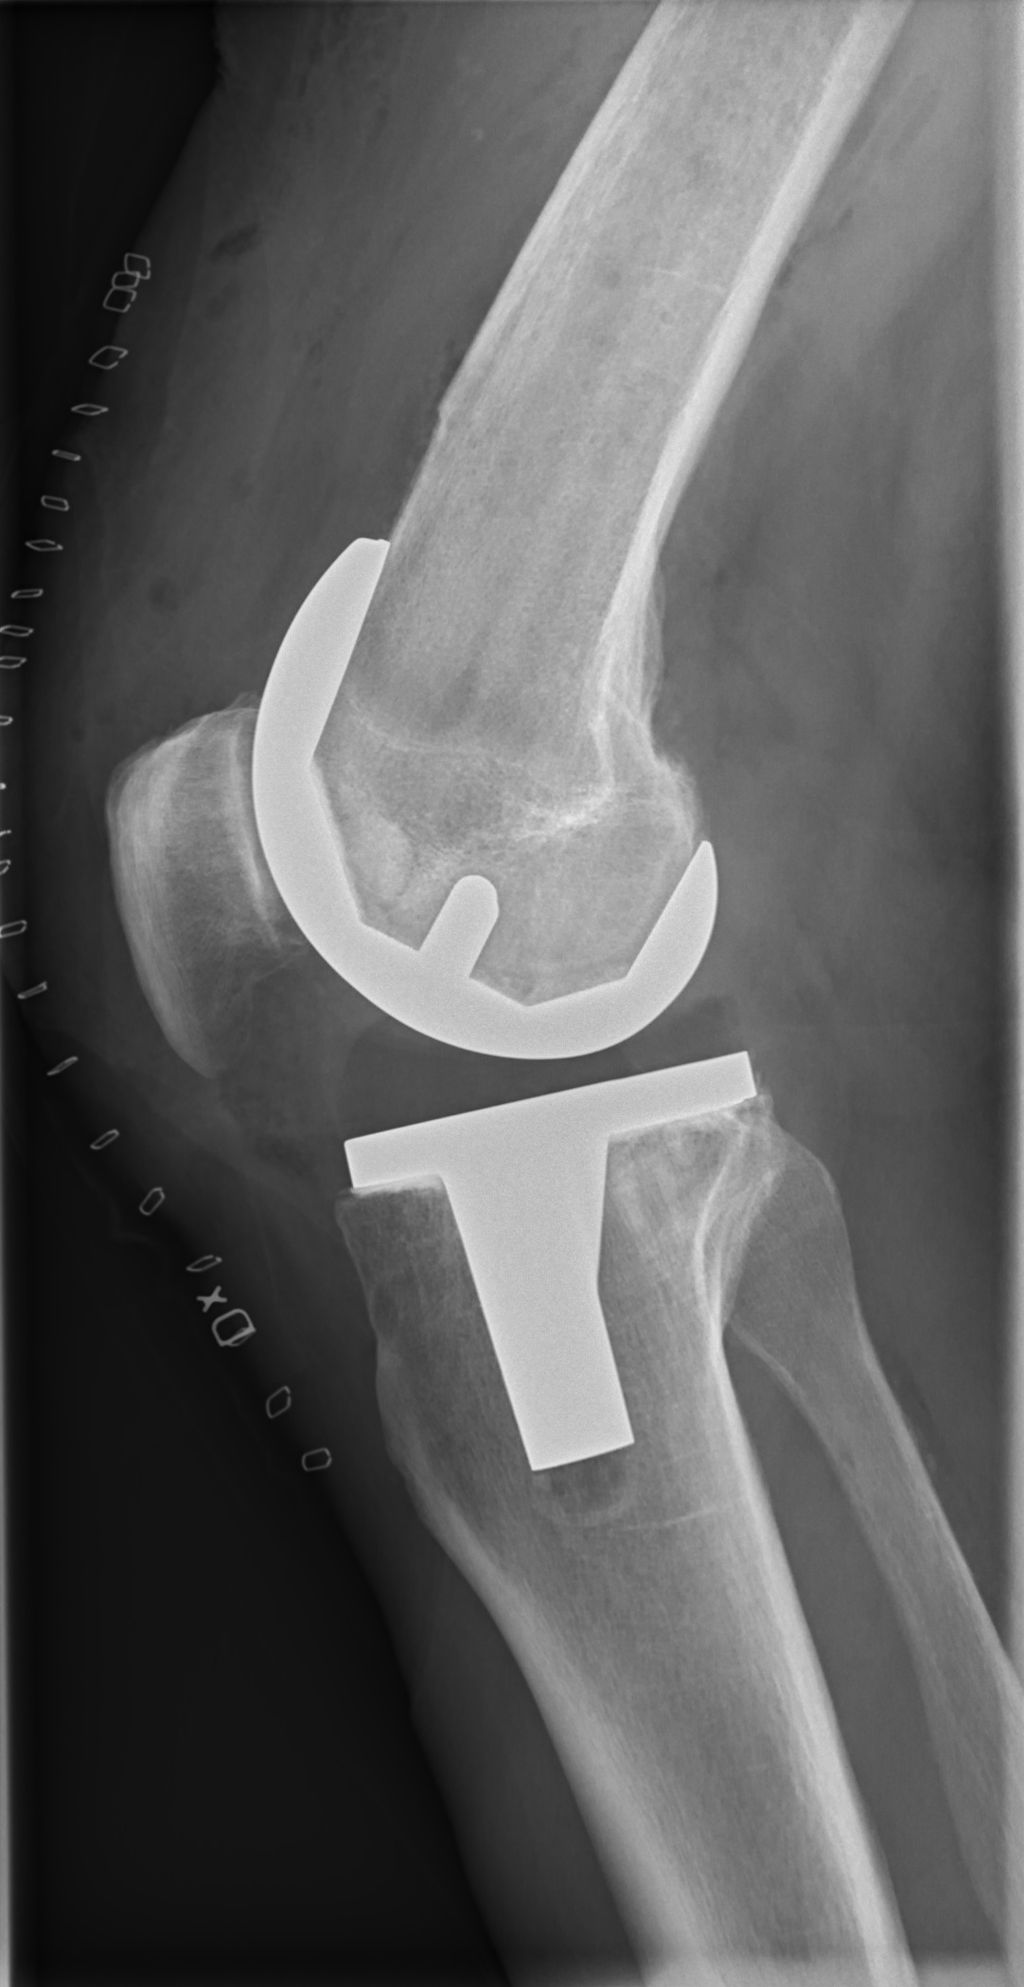

![]()

Surgical Interventions

In cases where physical therapy and orthotic devices are insufficient to correct inverted knees, we may consider surgical interventions. These procedures are typically reserved for severe deformities or when the condition leads to persistent pain and functional impairment. Surgical options vary depending on the underlying cause and severity of the knee inversion.

The most common surgeries include realignment osteotomies, where the bone is cut and repositioned, and ligament reconstructions to stabilize the knee joint. It’s essential to understand that surgery is followed by a period of rehabilitation to ensure the best possible outcome.